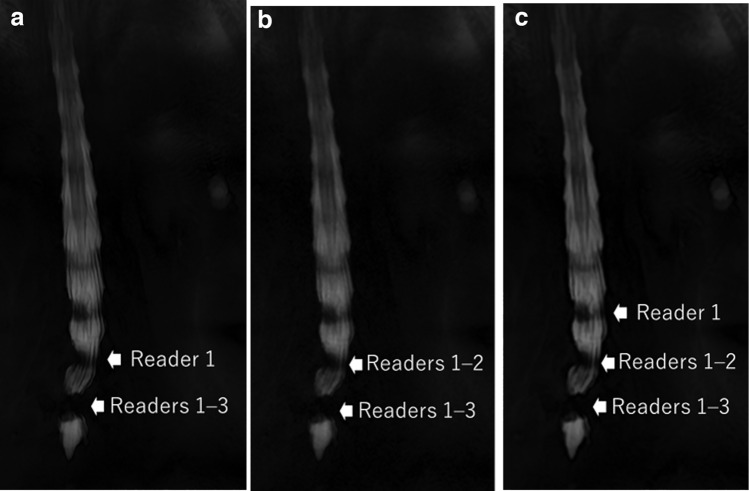

目的:探讨超分辨率深度学习重建(SR-DLR)是否能辅助评价腰椎管狭窄症。材料和方法:在本回顾性研究中,对40例患者(男性16例,女性24例;平均年龄59.4±31.8岁。利用磁共振成像数据,分别通过SR-DLR、深度学习重建(DLR)和传统的零填充插值(ZIP)重建MR脊髓图。三名放射科医生在不了解患者背景数据和MR重建信息的情况下,根据以下项目独立评估图像集:腰椎管狭窄影响的水平数量;和马尾描绘,清晰度,噪声,伪影,和整体图像质量。结果:SR-DLR、DLR和ZIP图像腰椎管狭窄程度的中位观察者间一致性分别为0.819、0.735和0.729。根据所有读者的评价,SR-DLR图像的马尾成像质量、图像清晰度、噪声和整体质量明显优于DLR和ZIP图像(p)。结论:与DLR和ZIP图像相比,SR-DLR提高了腰椎MR脊髓造影的图像质量,并且在评估腰椎管狭窄状态时与更好的观察者间一致性相关。

Material and methods: In this retrospective study, lumbar MR myelography of 40 patients (16 males and 24 females; mean age, 59.4 ± 31.8 years) were analyzed. Using the MR imaging data, MR myelography was separately reconstructed via SR-DLR, deep learning reconstruction (DLR), and conventional zero-filling interpolation (ZIP). Three radiologists, blinded to patient background data and MR reconstruction information, independently evaluated the image sets in terms of the following items: the numbers of levels affected by lumbar spinal stenosis; and cauda equina depiction, sharpness, noise, artifacts, and overall image quality.

Results: The median interobserver agreement in terms of the numbers of lumbar spinal stenosis levels were 0.819, 0.735, and 0.729 for SR-DLR, DLR, and ZIP images, respectively. The imaging quality of the cauda equina, and image sharpness, noise, and overall quality on SR-DLR images were significantly better than those on DLR and ZIP images, as rated by all readers (p < 0.001, Wilcoxon signed-rank test). No significant differences were observed for artifacts on SR-DLR against DLR and ZIP.

Conclusions: SR-DLR improved the image quality of lumbar MR myelographs compared to DLR and ZIP, and was associated with better interobserver agreement during assessment of lumbar spinal stenosis status.